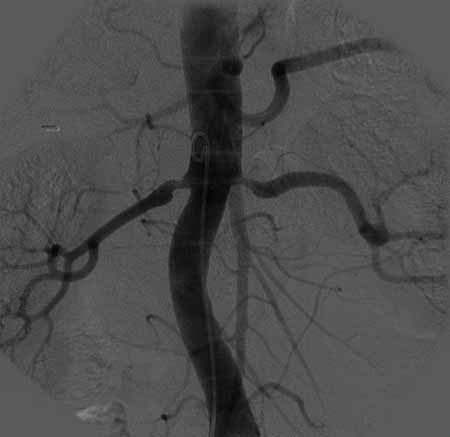

标题: DSA0088:肾动脉狭窄 [打印本页]

标题: DSA0088:肾动脉狭窄

女,63岁,高血压病史,160/100mmhg。

双侧肾动脉起始部狭窄,结合年龄考虑动脉粥样硬化所致.可进行球囊扩张或支架置入术.

凡出现血流动力学上有意义的肾动脉狭窄(≥70%)而无慢性终末期缺血性肾病的患者均应考虑行介入治疗或外科手术治疗。